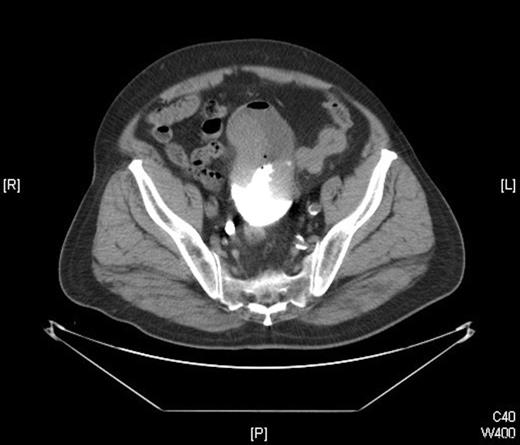

A 78 years old man presented with gross haematuria and serious irritative lower urinary tract symptoms. Ultrasonographic evaluation showed a mass arising from the posterior wall of bladder which completely filled the bladder lumen. Computed tomography (CT) showed a mass with hyperdense components that invaded perivesical fat about 10 cm diameter. There was no evidence of pelvic or abdominal lymphadenopathy on CT (Figure 1). Chest X-ray showed no evidence of metastasis. Eventually, we decided to perform a cystoscopy and a large, solitary, tough tumoral lesion was detected. Transurethral resection of the mass was executed and histopathological examination revealed a bladder tumor which contains both epithelial and stromal components.

CT scan showing the large heterogenous mass filling the bladder lumer